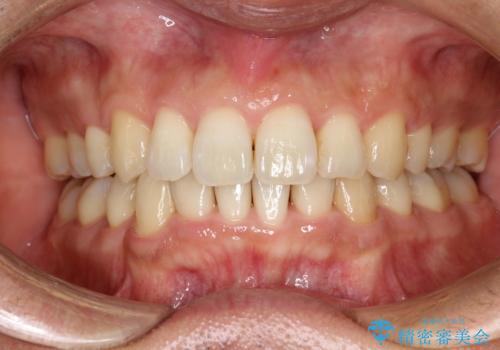

歯と歯の間を削って隙間を作って矯正をしています。

保定装置(後戻り防止のための装置)は、基本的にはマウスピースタイプをお渡ししているのですが、患者様のご希望で取り外ししないタイプを希望されたので、前歯の裏側を細いワイヤーで固定(ボンディングリテーナー)を作成しています。